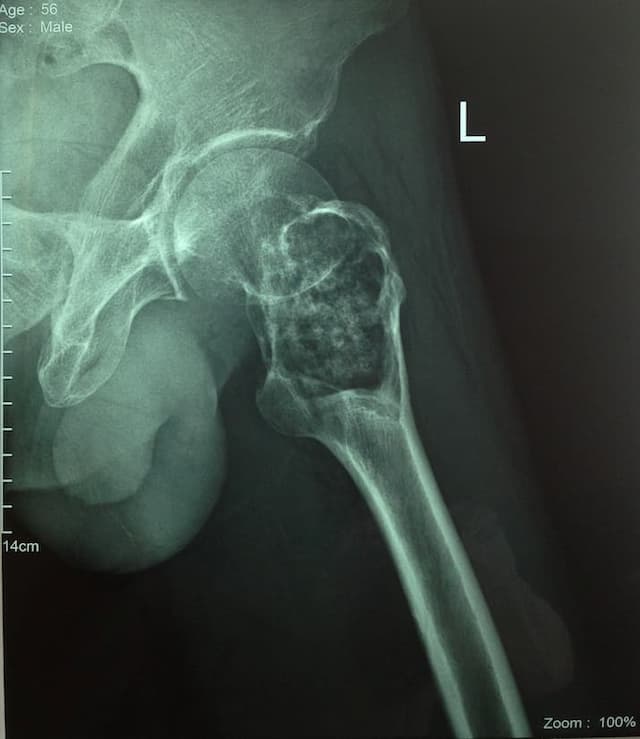

Түнхний үеийг хамарсан хавдарын үед хиймэл үе суулгах мэс заслын өмнөх болон дараах зураг

Түнхний үе бүтэн солих мэс засал (THA) image7Түнхний үе бүтэн солих мэс засал (THA) image8Түнхний үе бүтэн солих мэс засал (THA) image9